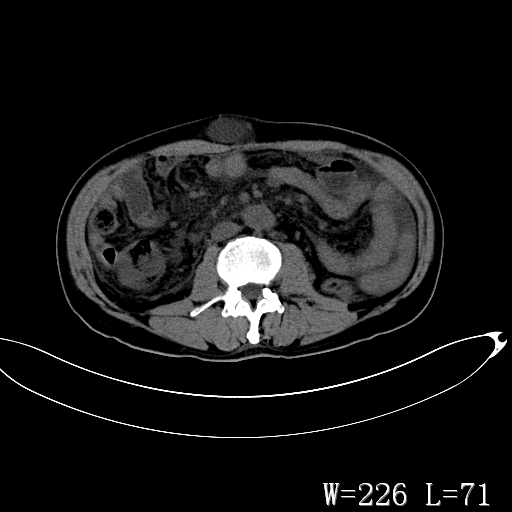

男,52岁,门脉高压断流术后1年,发现腹部肿物2月。

腹壁淋巴囊肿可能性大,不完全排外疝。

1)前腹壁中线区(脐上方)囊性占位性病变,考虑淋巴囊肿。2)腹水。